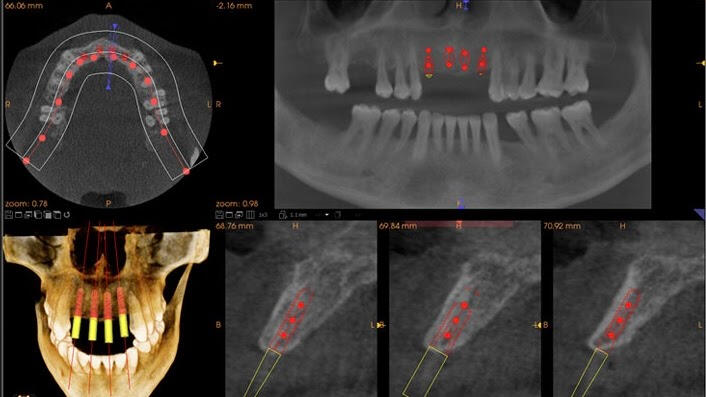

3D Imaging

Some patients have complicated conditions that require additional information to safely plan and successfully treat. Fortunately, technology is available in our office that delivers a complete3-Dimensional image of the jaws in just seconds. The 3D Cone Beam Computed Tomography (CBCT) is the newest and most advanced kind of imaging in dentistry. Our in house dental CT saves you the time and expense of additional trips to other specialty clinics.When necessary we use 3D imaging to make decisions about more complicated dental care such as:- Evaluations for implants

- Complex dental reconstruction

- Evaluating pathology